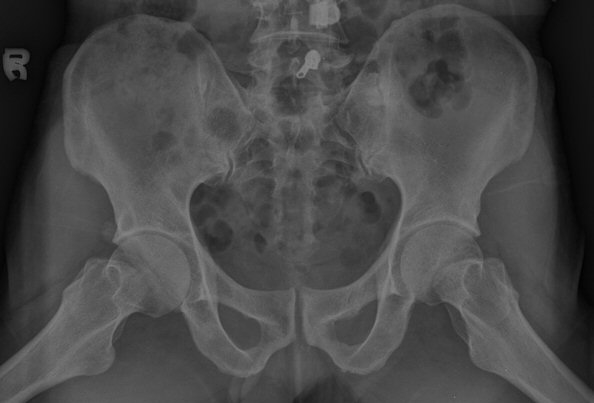

´Ü¼ø¹æ»ç¼±°Ë»ç

ÃÊÁø ½Ã ½ÃÇàÇÑ ¹æ»ç¼± ÃÔ¿µ»ó ÀüÇÏÀ屨 ºÎÀ§¿¡¼­ ¼®È¸È­ À½¿µÀÌ °üÂûµÇ°í, 3ÁÖ ÈÄ ½ÃÇàÇÑ ÃÔ¿µ¿¡¼­

¼®È¸È­ À½¿µ ¼Ò½ÇÀÌ È®ÀεÊ.